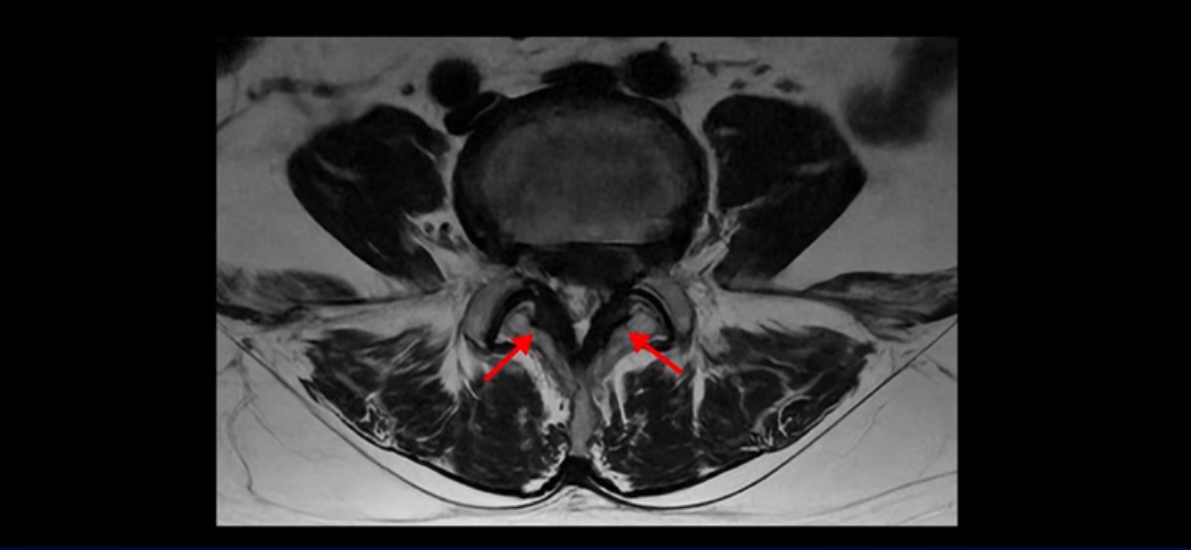

좌우 뒤쪽에는 황색 인대가 두꺼워져 있습니다.

앞에서는 디스크 수핵이 신경 공간으로 침범하고 뒤에서는 두꺼워진 인대가 신경 공간을 좁히고 있습니다.

이렇게 신경 공간이 좁아진 것을 협착이라고 합니다. 왼쪽으로 신경 구멍이 더 좁아져 있으니까 처음에는 왼쪽 엉덩이와 다리가 아팠는데 몇 년 동안 주사 맞으면서 버티다 보니까 오른쪽 다리까지 아프게 됩니다. 결국 양쪽 다리가 너무 아파서 5분 걷기도 힘들어지게 됩니다.

걸을 수 있는 거리는 점점 짧아지고 왼쪽 발의 근육이 빠져서 신발이 헐거워졌다는 얘기 들으셨죠? 이분 MRI를 보면

디스크 파열은 심해 보이나 신경 구멍이 좁아지는 협착증으로 보자면 저희 다른 치료 후기에 나오시는 협착증 환자분들의 MRI에 비해 신경 구멍은 넓은 편입니다. 그래서 신경이 정말 심하게 눌릴 때 나타나는 다리의 힘 빠짐 증상은 없었고 통증, 즉 아프다는 증상을 제일 심하게 호소하셨습니다.